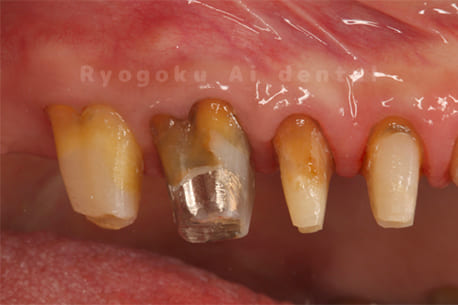

Case15

-

- 原因

- セラミッククラウン脱離、重度カリエス

- 治療内容

- クラウンレングスニング

- 治療費用

- 44,000円(別途被せ物の費用あり)

他院で行ったセラミックの被せ物が何度も取れてしまう、とのことでご来院されました。歯茎の中に埋まっている部分の歯を手術で出すことで被せ物が取れにくい環境にしました。今後、セラミックで被せ直しを行います。